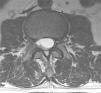

Case reportA male patient of 54 years of age was admitted to our hospital with 10 months’ evolution of lumbago with pain radiating to both lower extremities. In the last two months, his symptoms had gradually progressed with paraesthesia and saddle hypoesthesia, urinary incontinence and constipation. He reported no history of trauma or other spinal procedures. The neurological examination revealed cauda equina syndrome, urinary incontinence, loss of anal sphincter tone, paraesthesia of the lower extremities with a strength of 3/5 bilaterally and both proximally and distally, and bilateral patellar and achilles hyporeflexia. Magnetic Resonance Imaging (MRI) showed hyperintensity at the L2-L3 level in the T2 sagittal image (Fig. 1), while the axial image showed the same intraspinal, intradural and intramedullary feature to be heterogeneous, with the major component located centrally and a hypointense periphery (Fig. 2). It was decided to perform laminoplasty of L2 to L4, opening the dura mater, whereupon we observed that the major component was a central cystic lesion of friable, yellow-grey tissue. Consequently, the tumour was resected in its entirety. The histological examination revealed a mature teratoma with fully differentiated components (Figs. 3–6).

Images of the tumours obtained by Magnetic Resonance Imaging (MRI) guide the diagnosis of spinal teratoma.15 The morphological appearance on the MRI varies based on the location of the tumours. Intradural teratomas are often oval or lobulated heterogeneous masses, while extradural teratomas are more commonly found to have a “dumbbell” shape.5,6,15 Cases of extradural teratoma are frequently accompanied by malformation of the vertebral body, while intradural teratomas in adults are usually found under the dura mater, rarely invading the dura mater or vertebral body.3

ConclusionIntradural spinal teratomas are very rare, even more so in adults. The heterogeneous signal shown by MRI images can indicate the solid or cystic composition of the tumour lesion, which is extremely helpful for an early diagnosis of teratoma. The clinical picture is very non-specific, suggesting only compression of the spinal cord and/or medullary syndromes that could be caused by any other tumour lesion. Good outcomes are achieved with total surgical resection, as the clinical symptoms are caused primarily by compression of the spinal cord by the spinal teratoma. Extreme care is essential when resecting the tumour, in order to avoid breaking the cyst and disseminating its contents or post-surgical infections. Genetics is of little help, as there are no pathognomonic studies of this disease, and, as always with surgery, using histopathology to corroborate the result gives the most certain diagnosis.